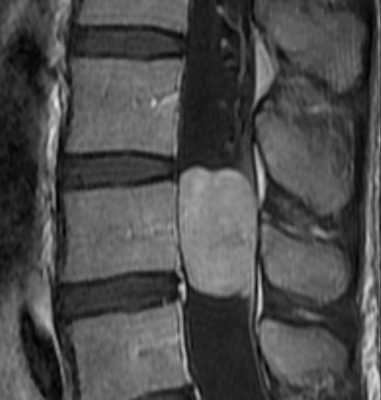

Типичными для хронической травмы изменениями при МРТ позвоночника являются миеломаляция, киста и атрофия спинного мозга. Посттравматический отёк спинного мозга приводит к его ишемии, с последующей демиелинизаций и глиозом. Патогенетической основой формирования кисты служит интрамедуллярная гематома. При ее резорбции остаётся локальная киста. Соединение кисты со спинномозговым каналом приводит к его расширению, а адгезия к нарушению оттока ликвора.

Локальная киста обычно наблюдается в месте наибольшего сдавления спинного мозга кистой или грыжей диска. Чаще они наблюдаются при травмах шейного отдела позвоночника. Киста при МРТ позвоночника имеет типичный ликворный сигнал в спинном мозге и может быть окружена зоной миеломаляции.

Сирингомиелитические кисты как отдалённое последствие спинальной травмы встречаются у 3-4% пациентов с неврологическими нарушениями. В целом, они относятся к отдалённым последствиям трамы, хотя известны случаи раннего формирования сирингомиелитических кист. Чаще кисты выявляются при МРТ грудном отделе спинного мозга. Замечена связь сирингомиелитических кист с деформацией позвоночного канала и посттравматическим его стенозом. В отличие от истинной сирингомиелии они развиваются на фоне атрофии и обычно не сопровождаются вздутием спинного мозга. Кисты наблюдаются с одинаковой частотой как выше, так и ниже уровня травмы. Протяжённость кисты может быть любой. Содержимое кисты обычно ликворное, но бывает и с примесью белка, что повышает сигнал от её содержимого на Т1-зависимых МРТ. На Т2-зависимых МРТ в кисте могут быть зоны потери сигнала, что отражает повышенное давление внутри неё. Отмечено, что дренаж кист в этих случаях наиболее эффективен. Изредка при МРТ в кистах встречаются перегородки.